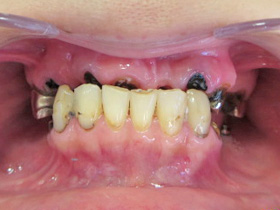

20代女性

今まで歯科が怖くて行けず、放置していた。前歯が痛くて来院。奥歯でも噛めず、前歯も綺麗にしたいと来院。今回は完治したい。

最初にインフォームドコンセントをしっかり行いました。それは、患者さんの協力無しでは治療はできません。本気で治したい!自分の歯ですから!と歯医者まかせではなく、歯科治療は患者さんとドクターとの共同作業になりますから。

まず虫歯で壊れている歯は根の先まで膿んでいたため、根管治療後、歯肉整形をしファイバーコアを使い土台を作りました。全ての歯を抜かずに残す事ができました。被せ物はメタルボンドを希望されてましたのでメタルボンドにて修復しました。この方は元々開口(オープンバイト)であった為上下が噛んでなかったため下の歯が生えてきた時と同じ形態を維持してたため審美的に上の歯並びをどうしたいかを相談したら下と同じ様に元々の状態に回復して欲しいと希望されましたので、その様に治療しました。奥歯も保険にて全て治療完成しました。

患者さんはちゃんと噛める様になった事と、長年放置してて無かった前歯が入りすごく喜んでもらえました。これで口元を気にしないで大口でも笑えますね。